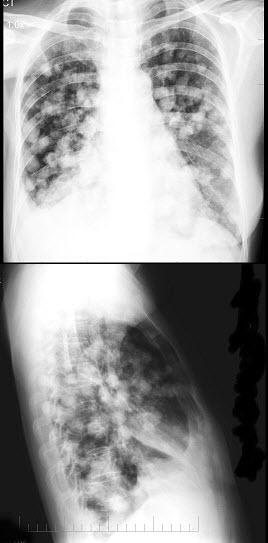

女,31岁,咳嗽发热1周,胸片检查如图,最可能的诊断是()

女,53岁,胸闷乏力数月,偶感胸痛,不发热,X线检查如图,最可能的诊断是()

A.原发性肺癌

B.亚急性血行播散型肺结核

C.肺转移瘤

D.细支气管肺泡癌

E.结节病